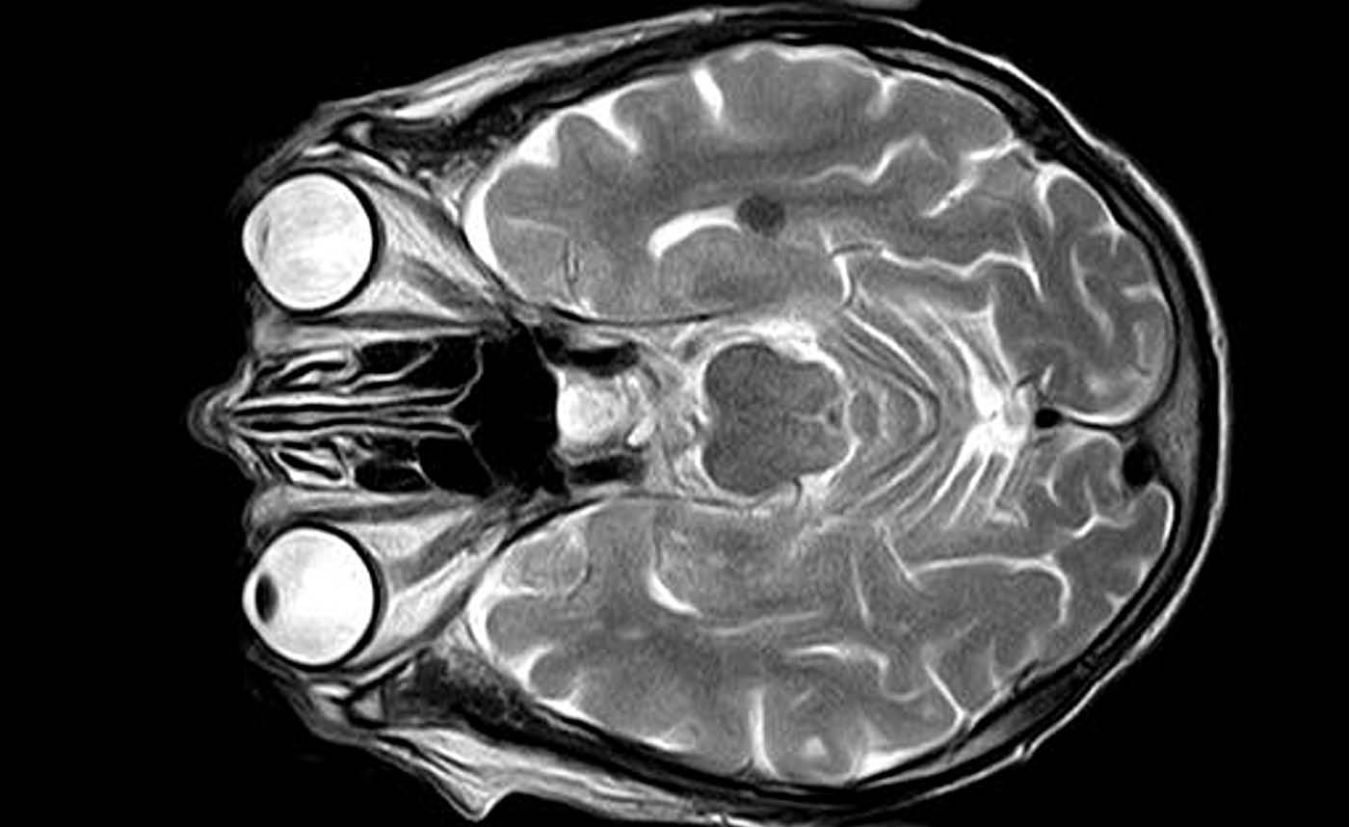

Elk jaar krijgen ongeveer 1500 jonge mensen tussen de 18 en 50 jaar in Nederland een beroerte (een herseninfarct of een hersenbloeding). Het zijn mensen die net aan een studie beginnen, een carrière aan het opbouwen zijn, een druk gezinsleven hebben, midden in het leven staan. En dan ineens worden ze overvallen door een beroerte. Ze kunnen eraan overlijden, maar ze kunnen het ook overleven, al dan niet (ernstig) geïnvalideerd.

Hoe vergaat het deze jonge mensen die een beroerte overleven? Daar is maar weinig onderzoek naar gedaan. Bovendien blijft het weinige onderzoek dat er is, de patiënten meestal niet lang volgen. Dat is nu wel gebeurd in het onderzoek van neurologen van het Radboudumc dat JAMA nu publiceert. Het gaat om een onderzoek bij meer dan 15.000 patiënten die op jonge leeftijd een beroerte kregen in de periode 1998 – 2010 en hoe het hen verging in de (vele) jaren daarna.